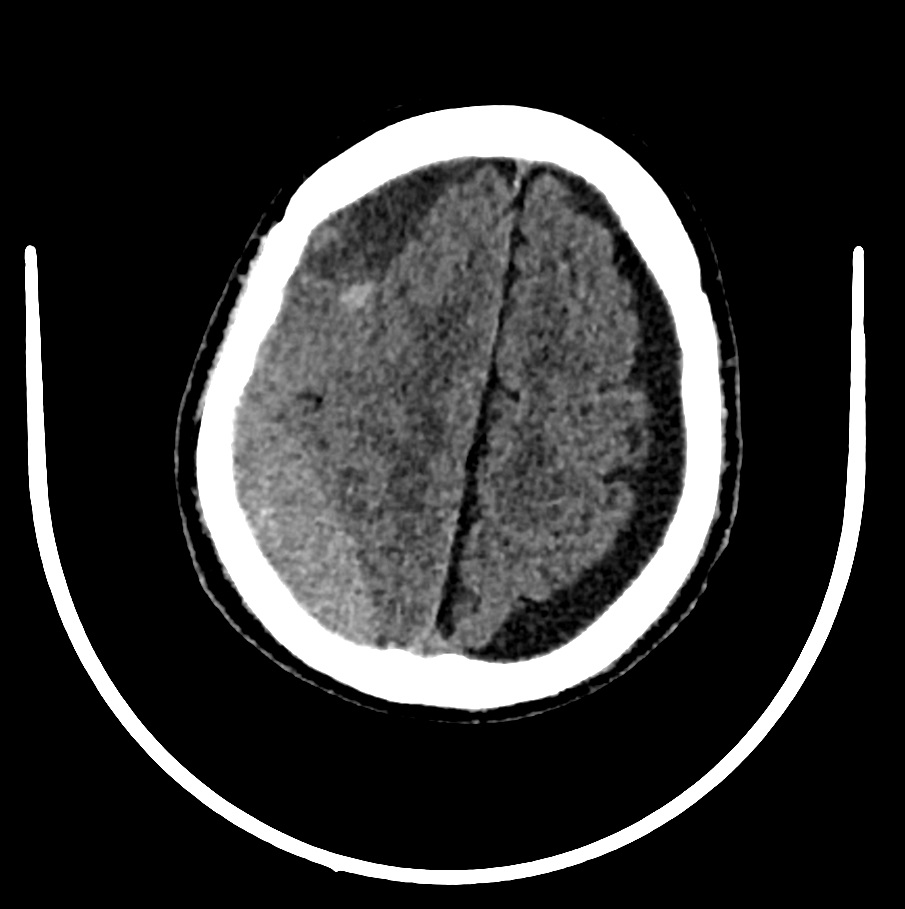

TAC cráneo: Hematoma subdural subagudo-crónico y efecto compresivo con obliteración de surcos frontoparietales.

Último TAC de control: Resolución del HSD derecho.